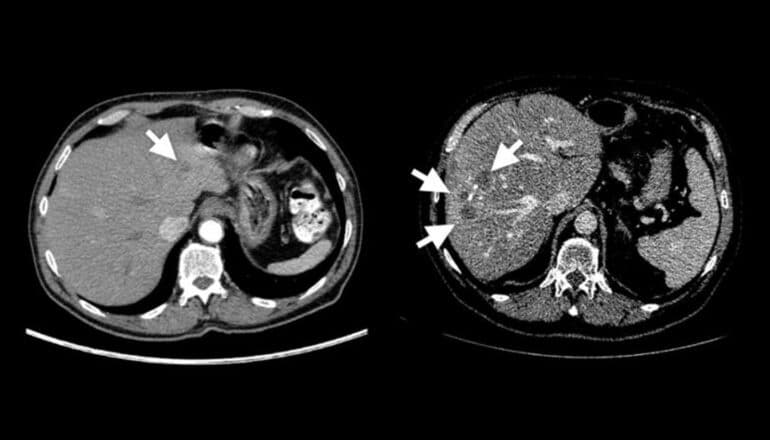

Two abdominal scans side by side show one has a real tumor and the other has several synthetic tumors.

The researchers say that the resulting synthetic tumors are hyperrealistic and have passed the Visual Turing Test—that is, even medical professionals usually confuse them with real tumors in a visual examination.